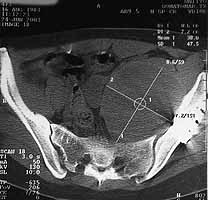

A week ago suddenly marked pain in the limb, irradiation to the foot, numbness/paresthesia of the tibia, lumbalgia. Neurosurgeon examined her and found no pathology. Xrays of the pelvis and lumbar spine show nothing unexpected. CT scans revealed some volume in the pelvis

Regarding case of large soft tissue mass in the pelvis 6 months after ORIF of acetabulum fracture. I would consider an ultrasound to see if it is solid or fluid filled and an MRI. It looks big and round and is suggestive of fluid. Keep in mind possible pseudo-aneurysm (careful about biopsy), or abscess. Soft tisssue neoplasia unrelated to the fracture possible.